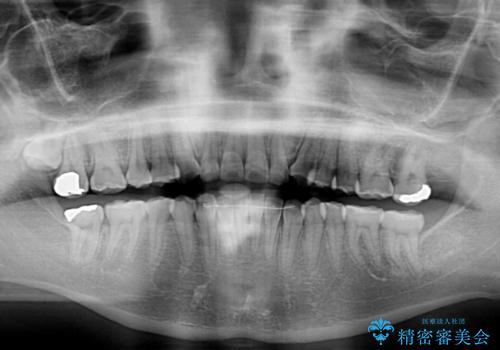

- 前歯のデコボコとクロスバイトが気になり、インビザラインによる矯正治療を希望して来院された患者様です。

上顎側切歯(上の真ん中から2番目の歯)が舌側転位している場合、無理して動かそうとすると歯髄壊死を起こすリスクが高い印象があります。

インビザライン単体でも治療は可能ですが、安全策としてインビザラインで歯列を移動する前に上顎前歯をワイヤー矯正で整え、その後上下歯列をインビザラインにて矯正治療を行うこととしました。

舌側転位している側切歯特有の、切縁の位置が不揃いであったり、根元が内側に引っ込んだ状態であったりという、インビザライン独特の仕上がりになることなく、きれいに整った歯列とすることができました。